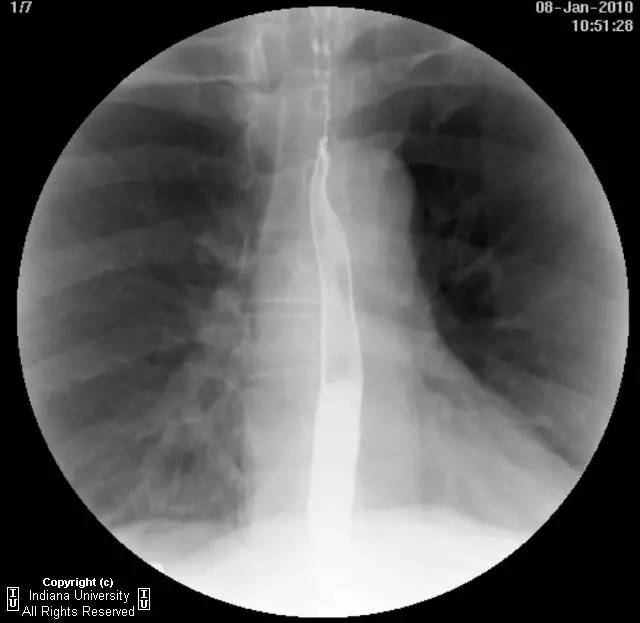

【影像学表现】下咽部正常,环咽肌功能正常。颈段食管无外生性病变压迫或异常扩张。胸中段食管长节段狭窄,逐渐移行为正常食管粘膜。大量小的烧饼样钡斑位于相应食管外呈浮萍样,与食管管腔无直接交通。稠或稀钡剂通过均无延迟。1cm钡剂片延迟通过,约30分钟后自动溶解。余食管动力正常。

【诊断】食管壁内假性憩室并长节段狭窄

Long segmentstricture with esophageal intramural pseudodiverticulosis